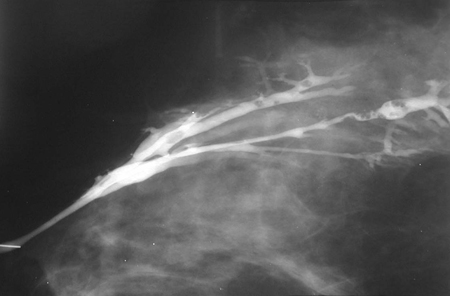

Ductografia demonstrando papilomas intraductais múltiplos

Cortesia da Dra. Nancy Pile, Universidade de Louisville; usado com permissão